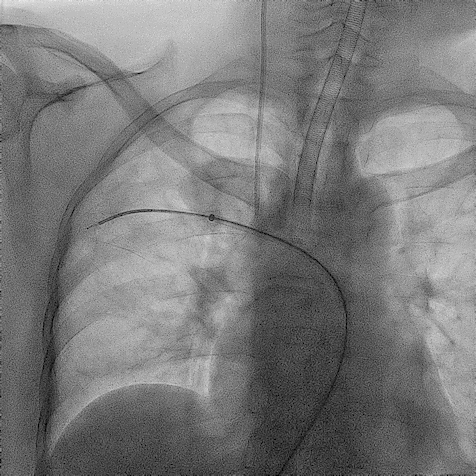

手术过程(一):

超选左肾静脉,左侧卵巢静脉,造影见卵巢静脉曲张明显,直径13 mm,盆腔大量曲张静脉显影。